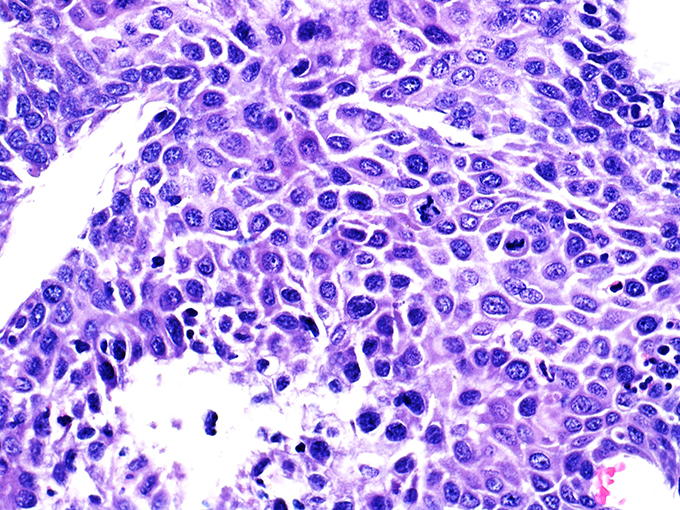

![]() Case 2

Soft Bx CIN 2 10x - Low Power |

Soft Bx CIN 2

40x - High Power